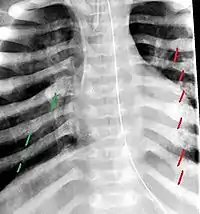

The material factual allegations of the amended complaint are as follows. Plaintiff was born on May 14, 1970. On repeated occasions during the first year of her life she was severely beaten by her mother and the latter's common law husband, one Reyes. On April 26, 1971, when the plaintiff was eleven months old, her mother took her to the San Jose Hospital for examination, diagnosis, and treatment. The attending physician was defendant Dr. Flood, acting on his own behalf and as agent of the defendant San Jose Hospital. At the time, the plaintiff was suffering from a comminuted spiral fracture of the right tibia and fibula, which gave the appearance of having been caused by a twisting force. Plaintiff's mother had no explanation for this injury. Plaintiff had bruises over her entire body. In addition, she had a non-depressed linear skull fracture which was then in the process of healing. Plaintiff demonstrated fear and apprehension when approached. Inasmuch as all plaintiff's injuries gave the appearance of having been intentionally inflicted by other persons, she exhibited the medical condition known as the battered child syndrome.

It is alleged that proper diagnosis of plaintiff's condition would have included taking X-rays of her entire skeletal structure, and that such procedure would have revealed the fracture of her skull. Defendants negligently failed to take such X-rays, and thereby negligently failed to diagnose her true condition. It is further alleged that proper medical treatment of plaintiff's battered child syndrome would have included reporting her injuries to local law enforcement authorities or juvenile probation department. Such a report would have resulted in an investigation by the concerned agencies, followed by a placement of plaintiff in protective custody until her safety was assured. Defendants negligently failed to make such report.

For example, the leading article by Kempe et al., op. cit., supra,[10] states that "A physician needs to have a high initial level of suspicion of the diagnosis of the battered-child syndrome in instances of subdural hematoma, multiple unexplained fractures at different stages of healing, failure to thrive, when soft tissue swelling or skin bruising are present, or in any other situation where the degree and type of injury is at variance with the history given regarding its occurrence . . . ." (Id., at p. 20.) Of the different types of fractures exhibited, an arm or leg fracture caused by a twisting force is particularly significant because "The extremities are the 'handles' for rough handling" of the child by adults. (Id., at p. 22.) The article also contains numerous recommendations to conduct a "radiologic examination of the entire skeleton" for the purpose of confirming the diagnosis, explaining that "To the informed physician, the bones tell a story the child is too young or too frightened to tell." (Id., at p. 18.) Finally, on the subject of management of the case it is repeatedly emphasized that the physician "should report possible willful trauma to the police department or any special children's protective service that operates in his community" (id., at p. 23) in order to forestall further injury to the child: "All too often, despite the apparent cooperativeness of the parents and their apparent desire to have the child with them, the child returns to his home only to be assaulted again and suffer permanent brain damage or death." (Id., at p. 24.)